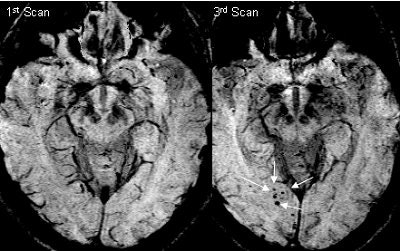

One potential application for SWI is in Alzheimer's disease and vascular dementia. A longitudinal study done in conjunction with Loma Linda University in Loma Linda, CA, has revealed a propensity of microbleeds in a major fraction of subjects with mild cognitive impairment. When many microbleeds were present at the start of the study, these patients usually progressed to become progressively impaired or dementia cases. Several ongoing studies around the world are focusing on detecting microbleeds as a marker for aging and dementia. This work by the Loma Linda group -- under the direction of Dr. Wolff Kirsch, with analysis by the Wayne State group -- may be the first of its kind to successfully demonstrate SWI as a surrogate marker for potential vascular dementia based on microbleed detection.

| SWI and aging: A connection with cerebral amyloid angiopathy. These SWI images from a 1.5-tesla scanner show a growth in the number of microbleeds over nearly two years. It is believed that these may be caused by cerebral amyloid angiopathy. This particular subject went on to develop progressive cognitive impairment (Alzheimer's disease). Image courtesy of E. Mark Haacke, Ph.D., Wayne State University, Detroit, and Dr. Wolff Kirsch, Loma Linda University, Loma Linda, CA. |